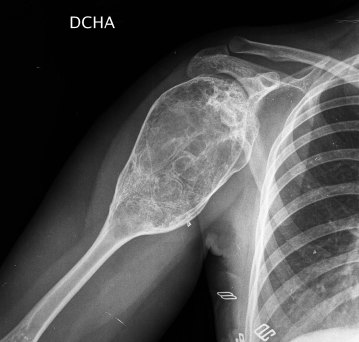

SIGNO DE LA BURBUJA O AMPOLLA DE HUESO

El Signo de la burbuja o ampolla de hueso (blister of bone) hace referencia a una lesión ósea lítica, que insufla el hueso a modo de burbuja, que adelgaza la cortical y que presenta finos septos en su interior. La cortical puede romperse, de forma espontánea por el crecimiento del tumor o con pequeños traumatismos, por lo que no es infrecuente el sangrado tanto en el interior de la lesión como en los tejidos adyacente. Este signo es muy característico de quiste óseo aneurismático.